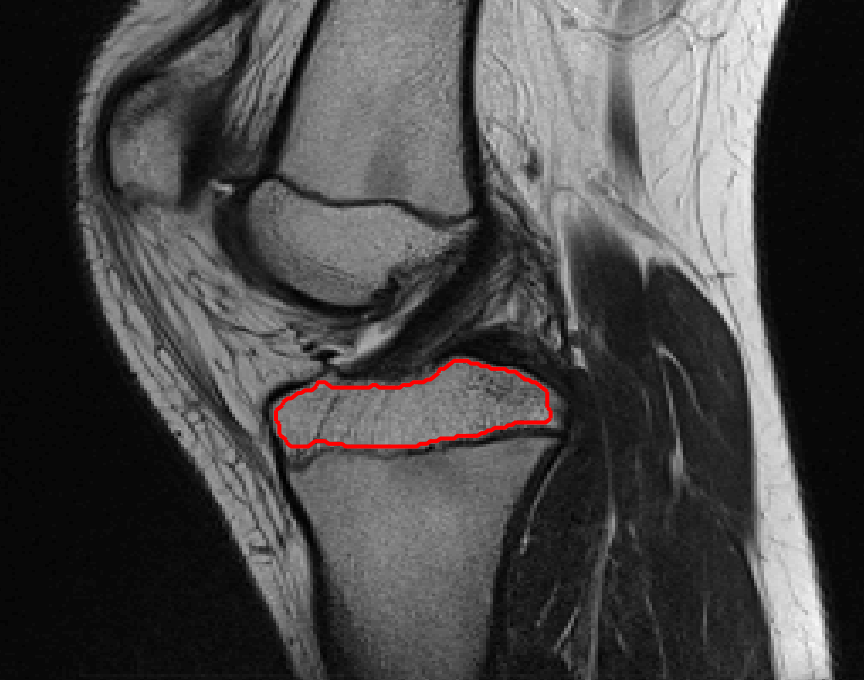

Test 1 – Comparison of models M1 – M7.

In this test we give the segmentation results for models M1 – M7 for the two challenging test images shown in Figure 9. The marker and anti-marker sets used in the experiments are also shown in this figure. After extensive parameter tuning, the best final segmentation results for each of the models are shown in Figures 10 and 11. For M1 – M4 we obtain incorrect segmentations in both cases. In particular, the results of M2 and M4 are interesting as the former gives poor results for both images, and the latter gives a reasonable result for Test Image 1 and a poor result for Test Image 2. In the case of M2, the regularisation term includes the edge detector and the distance penalty term (see (4)). It is precisely this which permits the poor result in Figures 10(b) and 11(b) as the edge detector is zero along the contour and the fitting terms are satisfied there (both intensity and area constraints) – the distance term is not large enough to counteract the effect of these. In the case of M4, the distance term and edge detector are separated from the regulariser and are used to weight the Chan-Vese fitting terms (see (9)). The poor segmentation in Figure 11(b) is due to the Chan-Vese terms encouraging segmentation of bright objects (in this case), weighting ω𝜔\omega enforces these terms at all edges in the image and near \mathcal{M}. In experiments, we find that M4 performs well when the object to segment is of approximately the highest or lowest intensity in the image, however when this is not the case, results tend to be poor. We see that, in both cases, models M5 and M6 give much improved results to M2 and M4 (obtained by incorporating the geodesic distance penalty into each). The proposed Geodesic Model M7 gives an accurate segmentation in both cases. It remains to compare M5, M6 and M7. We see that M5 is a non-convex model (and cannot be made convex [39]), therefore results are initialisation dependent. It also requires one more parameter than M6 and M7, and an accurate set \mathcal{M} to give a reasonable area constraint in (4). These limitations lead us to conclude M6 and M7 are better choices than M5. In the case of M6, it has the same number of parameters as M7 and gives good results. M6 can be viewed as the model M7 with weighted intensity fitting terms (compare (18) and (30)). Experimentally, we find that the same quality of segmentation result can be achieved with both models generally, however M6 is more parameter sensitive than M7. This can be seen in the parameter map in Figure 12 with M7 giving an accurate result for a wider range of parameters than M6. To show the improvement of M7 over previous models, we also give an image in Figure 13 which can be accurately segmented with M7 but the correct result is never achieved with M6 (or M3). Therefore we find that M7 outperforms all other models tested M1 – M6.

Refer to caption

(a) M1 (Left to right:) Test Image 2 with markers (red) and anti-markers (blue), foreground segmentation and background segmentation (we used published software, no parameter choice required).

(b) M2 λ=1𝜆1\lambda=1, γ=15𝛾15\gamma=15.

(c) M3 λ=5𝜆5\lambda=5, θ=1𝜃1\theta=1.

(d) M4 λ=1/8𝜆18\lambda=1/8.

(e) M5 λ=1,γ=15,θ=110formulae-sequence𝜆1formulae-sequence𝛾15𝜃110\lambda=1,\gamma=15,\theta=\frac{1}{10}.

(f) M6 λ=15,θ=1formulae-sequence𝜆15𝜃1\lambda=15,\theta=1.

(g) M7 λ=10,θ=1formulae-sequence𝜆10𝜃1\lambda=10,\theta=1.

Figure 11: Visual comparison of M1 – M7 results for Test Image 2. M1 segmented part of the object, M2 – M4 failed to segment the object, M5, M6 and M7 correctly segmented the object.